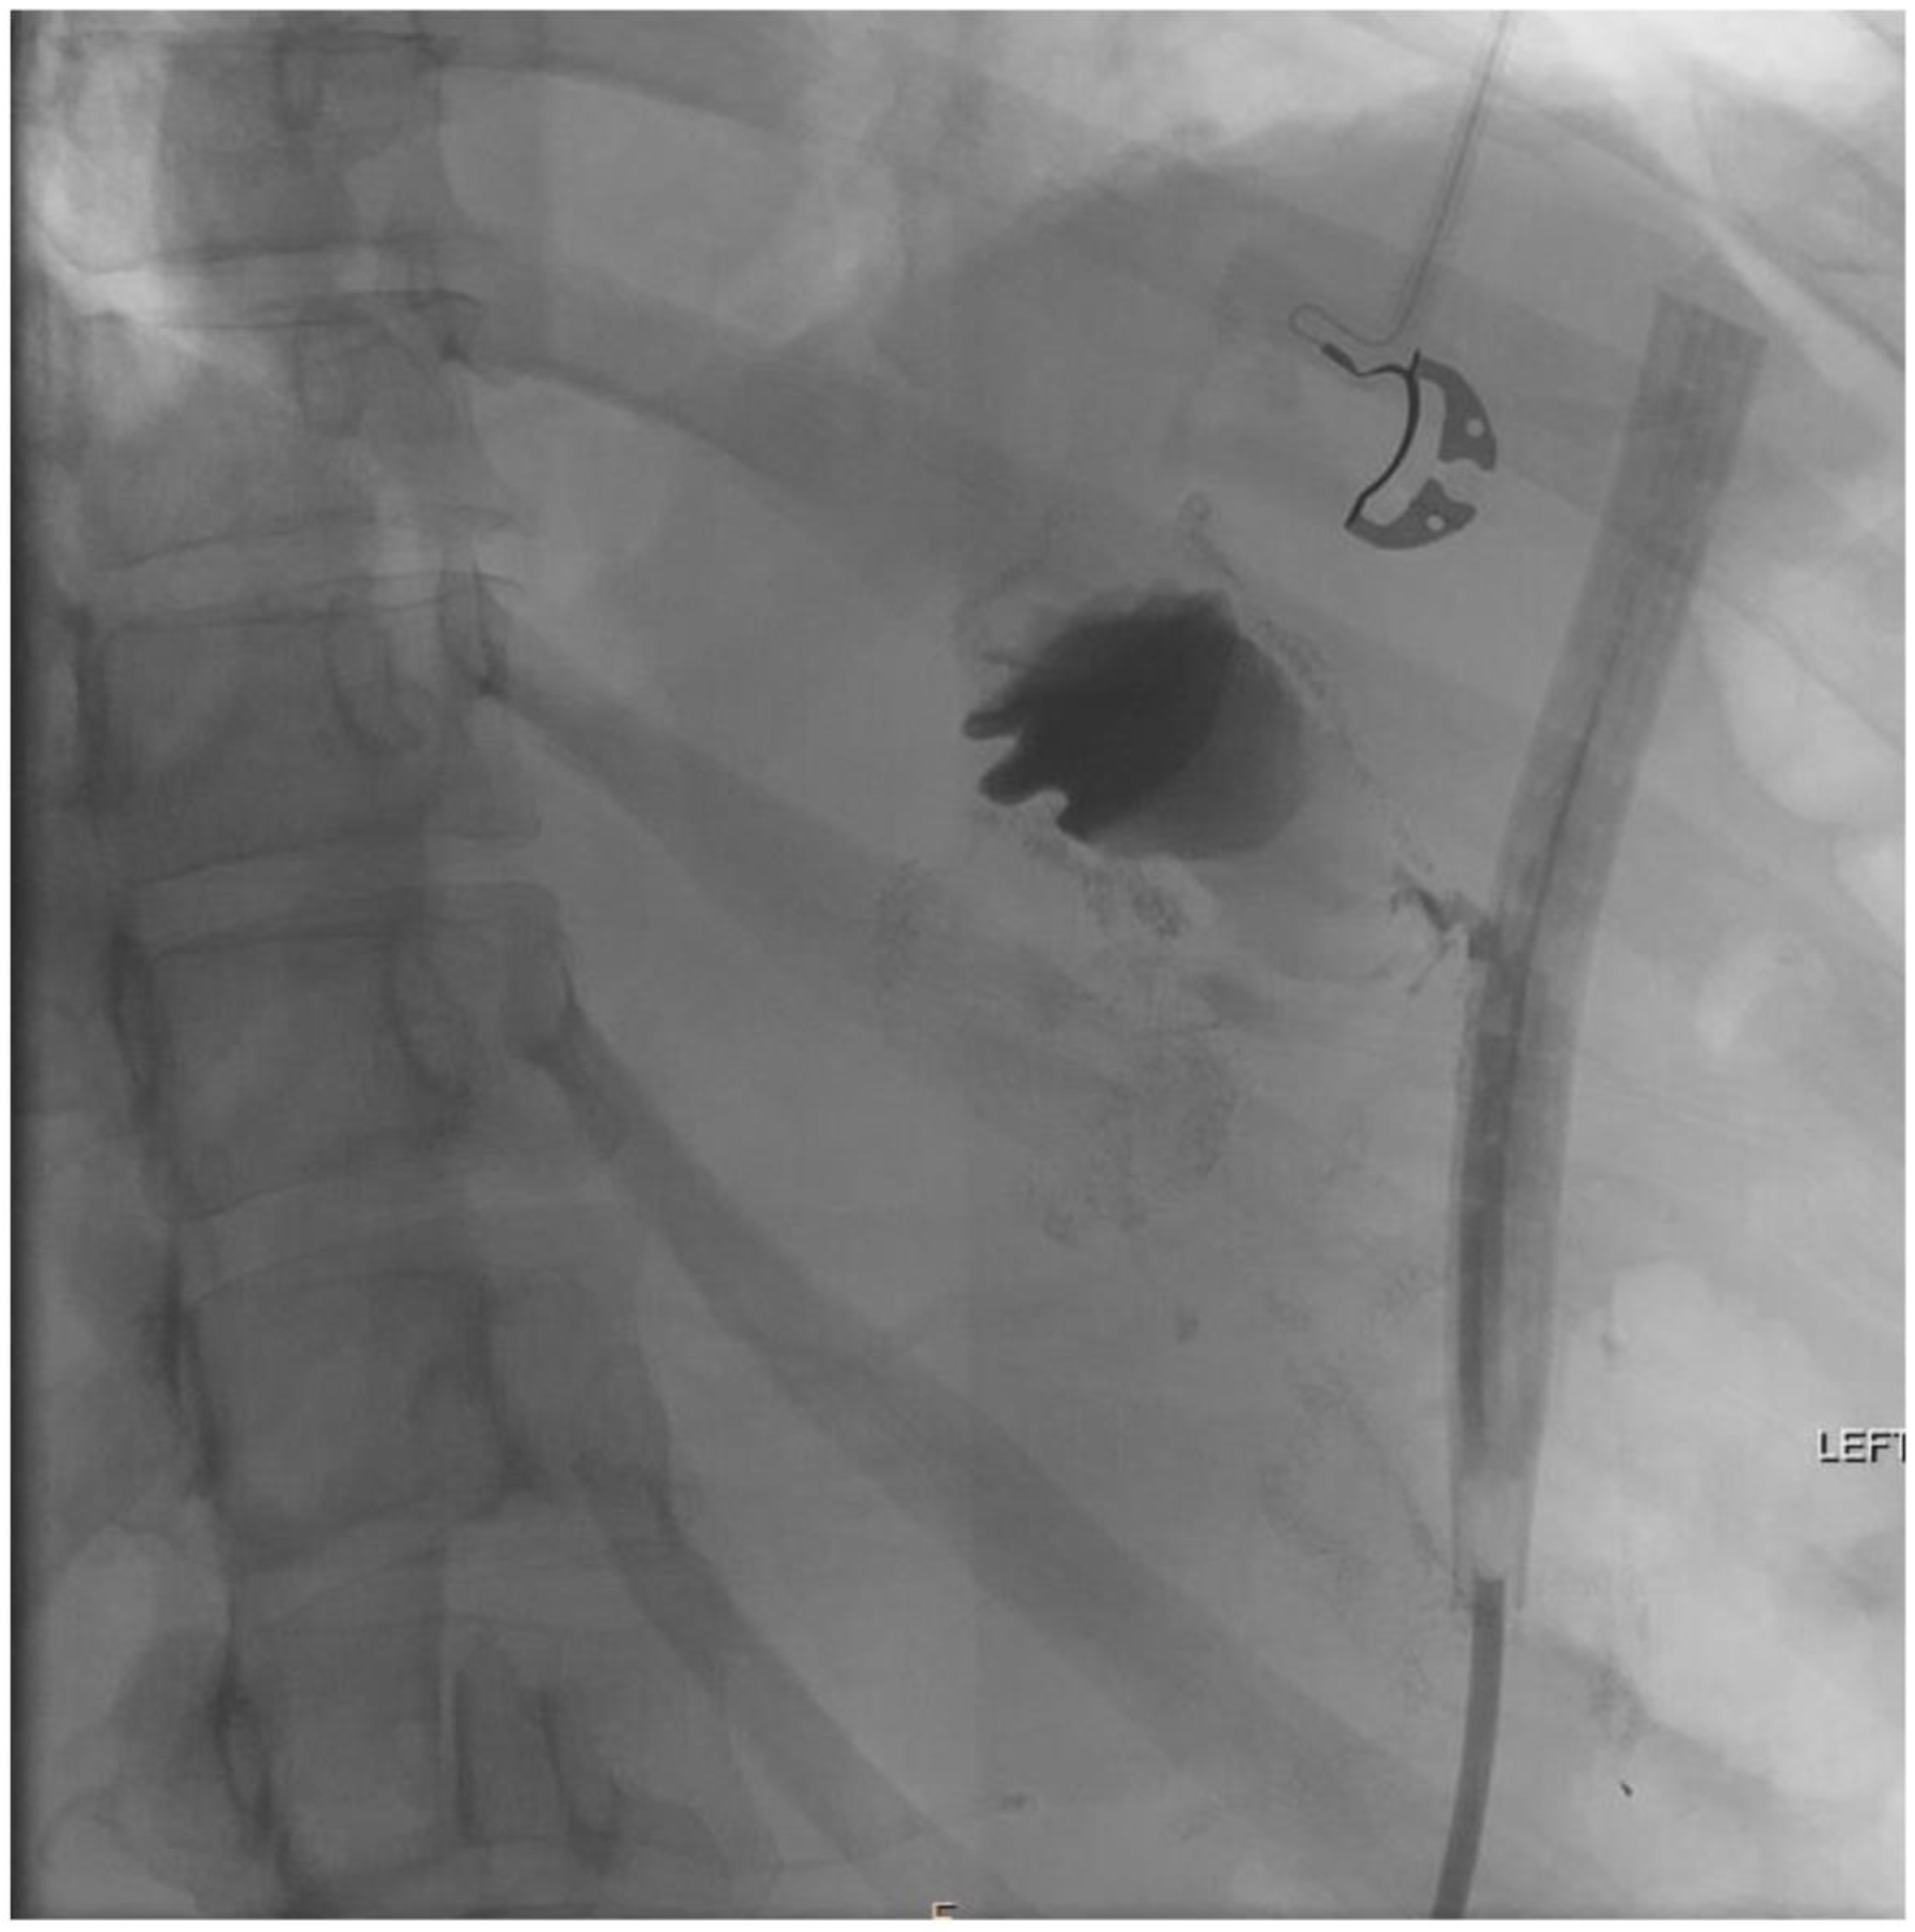

2. Detailed Case Description